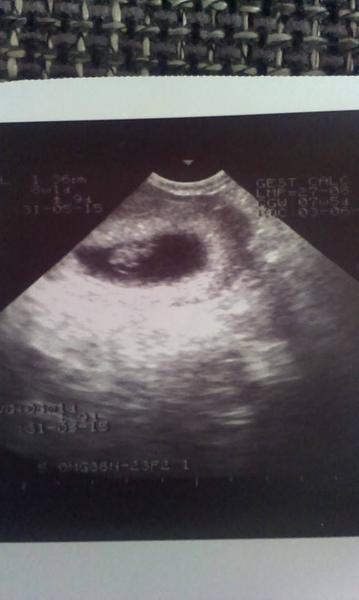

@karlos12 určitě bude vše vpořádku,to je jasný 🙂 taťka ještě neviděl,první sem mu to chtěla taky poslat,ale pak sem si říkala že k tomuhle ještě opravdu bude potřebovat výklad kde je co takže tak 😀 a slyšet jsem ho neslyšela,dr má starší utz,proto asi ani ty fotky nebudou zrovna super,ale vidět mi to opravdu stačí 🙂 teď mám obavy že mi budou dělat utz až na tom screeningu takže to bych si teda počkala sakja dlouho,no uvidíme 🙂 teď ještě letím na jednu injekci do toho ramene a na další už nepůjdu

@majkylove Gratuluju 🙂 Jsem ráda, že se naše řady zase rozrostly 😉 Je to paráda poprvé toho prcka vidět, co?

jinak 3.11 si jdu pro neschopenku a 12.11 mám už odběry a průkajdu 😵 a už sme dostali žádanku a mám se objednat na ten první screening tak hlavně aby tam bylo vše jak má,to bude nejdůležitější a tam už bysme měli mít krásnou fotečku 🙂